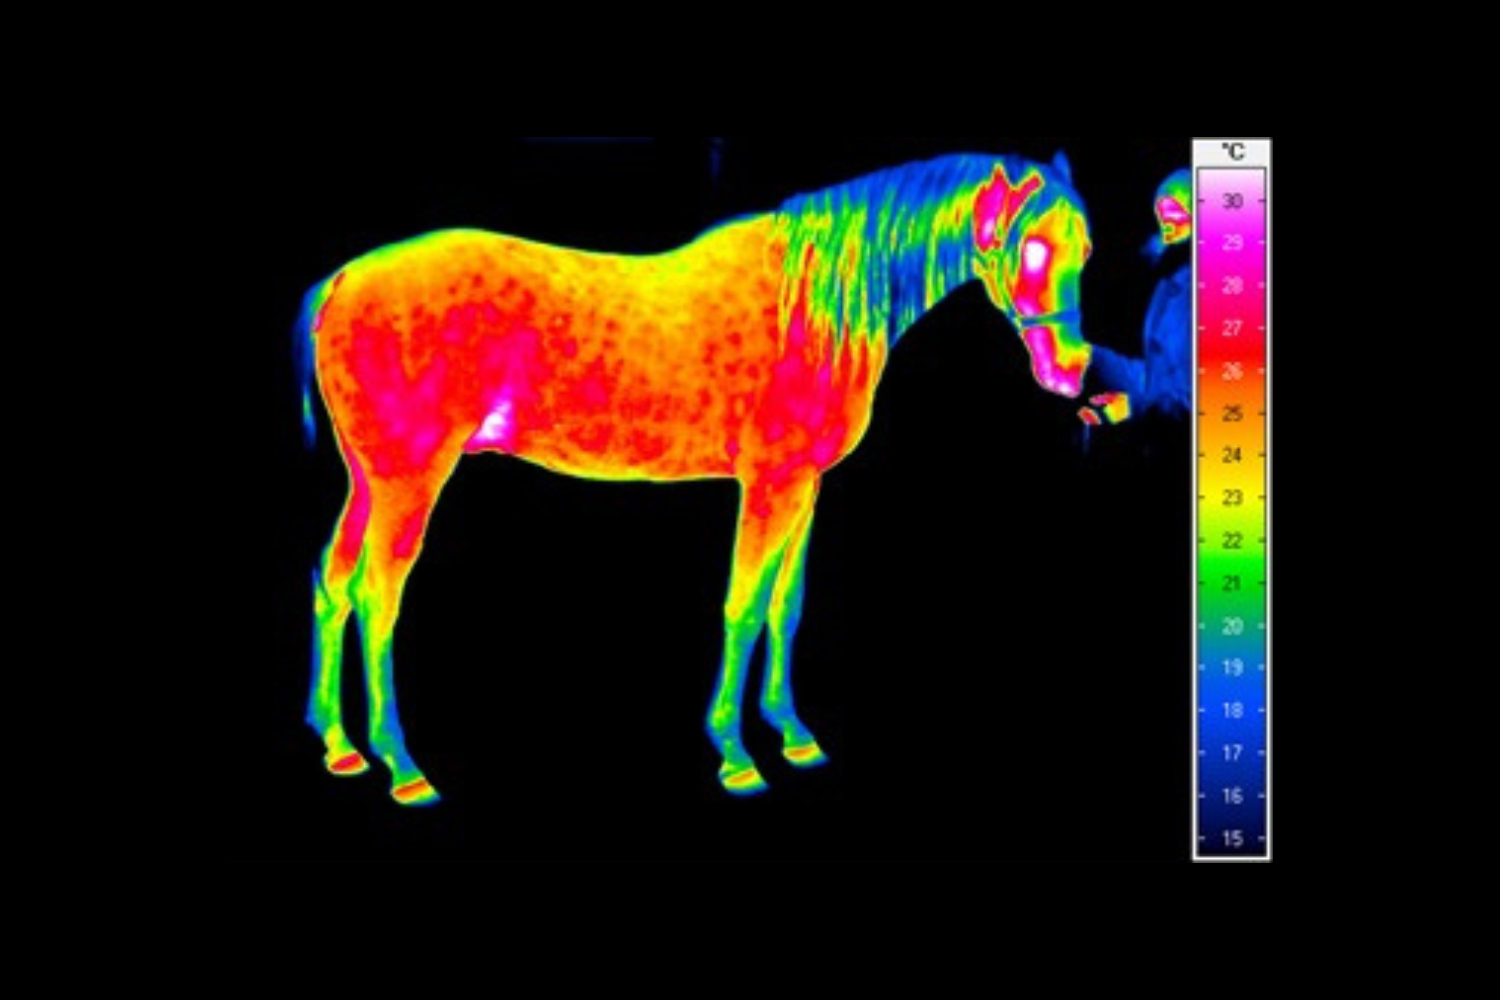

Termografia umożliwia nieinwazyjny pomiar rozkładu temperatury na powierzchni ciała konia. Wynikiem badania jest obraz – termogram, w którym poszczególne barwy odpowiadają określonym zakresom temperatur. Uzyskany rozkład cieplny odzwierciedla przede wszystkim ukrwienie tkanek powierzchownych, aktywność metaboliczną mięśni oraz właściwości izolacyjne skóry i okrywy włosowej.

W warunkach prawidłowych rozkład temperatury ciała konia charakteryzuje się wysokim stopniem symetrii pomiędzy lewą i prawą stroną. Najwyższe wartości temperatur obserwuje się w okolicach dobrze unaczynionych, takich jak oczy, nozdrza czy większe masy mięśniowe, natomiast najchłodniejsze obszary obejmują dalsze odcinki kończyn. Odstępstwa od tego wzorca – zwłaszcza asymetrie przekraczające około 1°C – mogą wskazywać na zaburzenia fizjologiczne lub rozwijające się procesy zapalne.

W medycynie weterynaryjnej i fizjoterapii najszersze zastosowanie termografia znalazła w ocenie dalszych odcinków kończyn, które są szczególnie narażone na urazy w trakcie treningu i użytkowania sportowego.

Metoda ta pozwala na identyfikację obszarów o podwyższonej temperaturze, związanych z zapaleniem ścięgien, więzadeł, torebek stawowych czy okostnej, często jeszcze przed pojawieniem się wyraźnych objawów klinicznych. Oprócz kończyn, istotnym obszarem zastosowania termografii jest grzbiet konia. Zaburzenia w obrębie mięśni przykręgosłupowych, więzadeł nad- i międzykolcowych czy stawu biodrowo-krzyżowego często mają charakter złożony i nie zawsze są łatwe do jednoznacznego rozpoznania przy użyciu standardowych metod. Termografia umożliwia wizualizację zmian w aktywności cieplnej tych struktur, co może wskazywać miejsca przeciążenia, bólu lub kompensacji ruchowych.

W praktyce szczególnie cenne okazuje się wykorzystanie termografii w przypadkach, gdy problemy kończyn i grzbietu wzajemnie na siebie oddziałują. Analiza całościowego rozkładu temperatury ciała pozwala spojrzeć na konia jako na funkcjonalną całość, a nie jedynie zbiór odrębnych struktur anatomicznych.